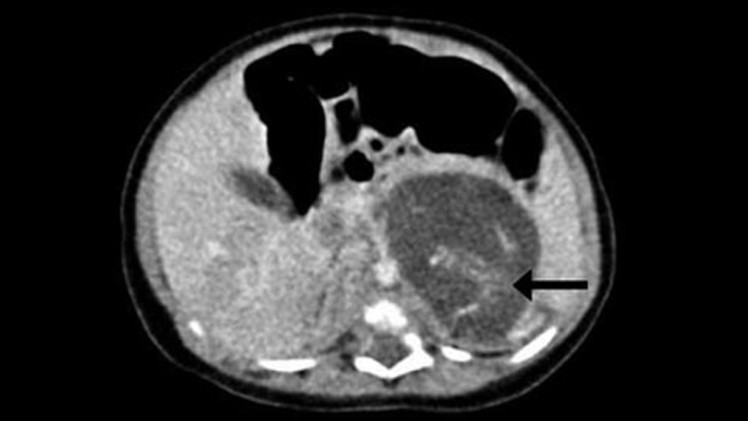

أظهر تصوير جسم جنين المولودة بالموجات فوق الصوتية الذي أجري قبل ولادتها وجود انتفاخ غريب في منطقة بطنها. وفي النتيجة أجرى الأطباء عملية لها بعد ثلاثة أسابيع من الولادة، حيث وجدوا جنينين بين كبدها وكليتها بوزن 9.3 غرام و14.2 غرام، ما يوافق فترتي الحمل لمدة سبعة وتسعة أسابيع.